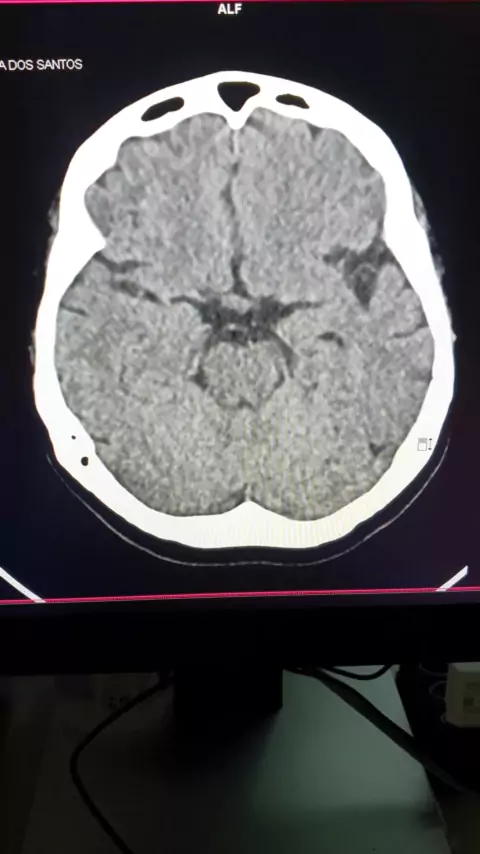

tomografia computadorizada de crânio